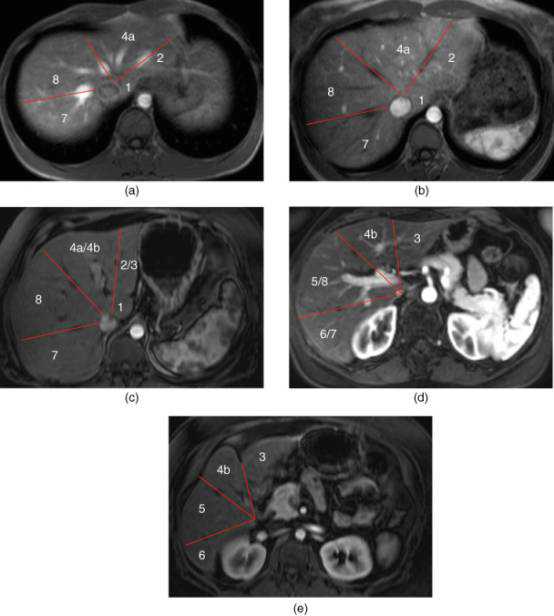

MRT1及增强扫描动脉期图像:

(1)肝上部水平:由肝中静脉、肝右静脉、镰状韧带分段。

(2)门静脉左支水平:门静脉左支将肝分为上下部分,上方II和Iva,下方III和IVb。门静脉左支比右支位置高。

(3)门静脉右支水平:该水平门静脉右支将肝右叶分为上部(VII和VIII)和下部(V和VI)。

(4)脾静脉水平:脾静脉较门静脉右支低。可见III、IVb、V、VI段。

肝左右叶(IV段与V、VIII段)分界:沿胆囊窝上方肝中静脉至下腔静脉(下图红线)。

肝左叶(内侧II、III段与外侧IV段)分界:沿镰状韧带和肝左静脉、肝中静脉汇合处下腔静脉连线(下图蓝线)。

肝右叶(前侧V/VIII段与后侧VI/VII段)分界:沿下腔静脉下方肝右静脉至肝脏边缘(下图绿线)。

尾状叶:尾状叶(I段)在后方,尾状叶与其他叶不同的是,它经常经静脉直接与下腔静脉,而不通过肝静脉主干,也有可能同时接受门静脉左右支的血供。(下图C)